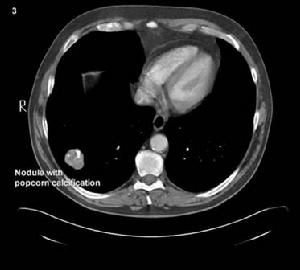

其他輔助檢查:X 線胸片肺中下野斑片陰影,少數為大片陰影,片狀濃密影中見透亮區,呈多發性。有胸腔積液者見胸腔積液之X 線徵象。